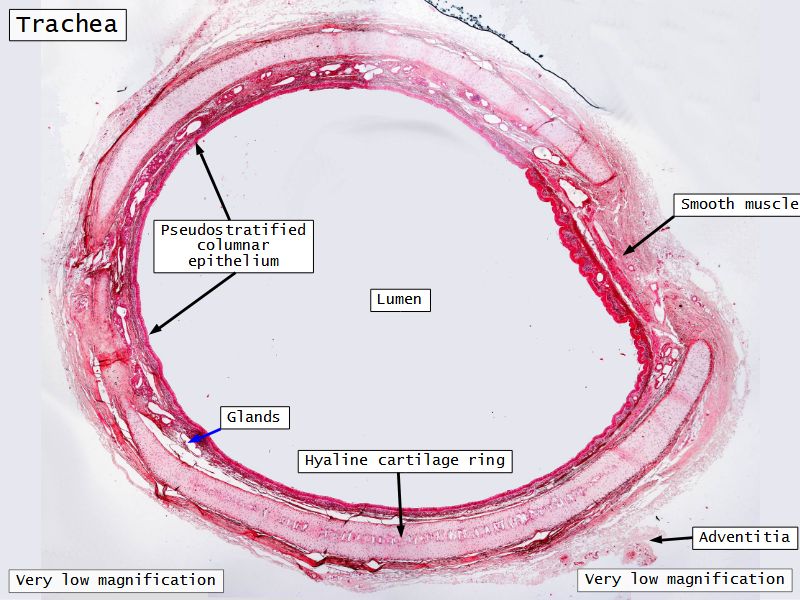

Respiratory epithelium

- Pseudostratified

- Ciliated

- Columnar

- Epithelium with

- 4 Cells

- Ciliated columnar cells

- Non-ciliated columnar cells

- Goblet cells

- Basal cells